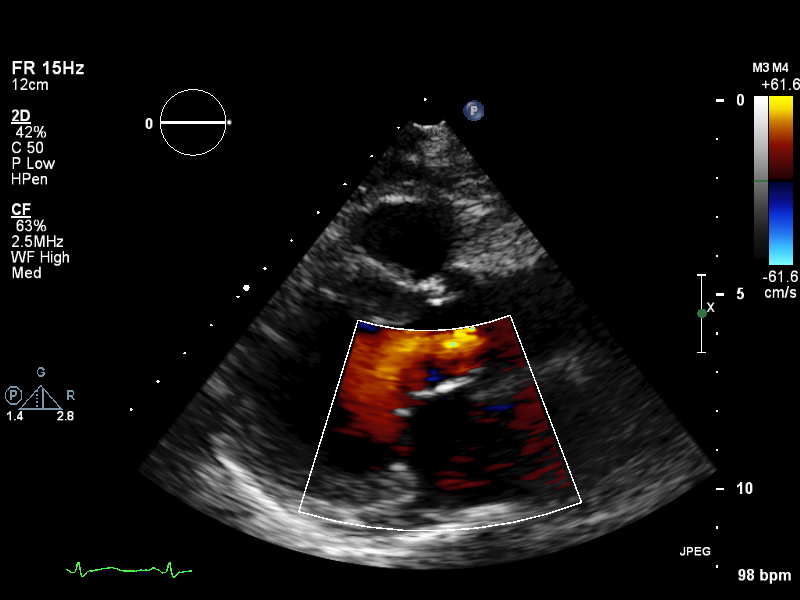

Apical (16 views)

ImageView NameDescription

a4ch-full a4ch-full Apical 4-chamber showing the full depth of all four chambers (no LV/RV focus)

a4ch-ias a4ch-ias Apical 4-chamber, focused on the inter-atrial septum

a4ch-la a4ch-la A4CH with Doppler near MV/LA or 2D covering full LA, not full LV

a4ch-lv a4ch-lv A4CH covering the whole depth of the LV, not the whole depth of the LA

a4ch-ra a4ch-ra Apical 4-chamber focused on the right atrium, or colour Doppler on TV/RA

a4ch-rv a4ch-rv Apical 4-chamber focused on the right ventricle